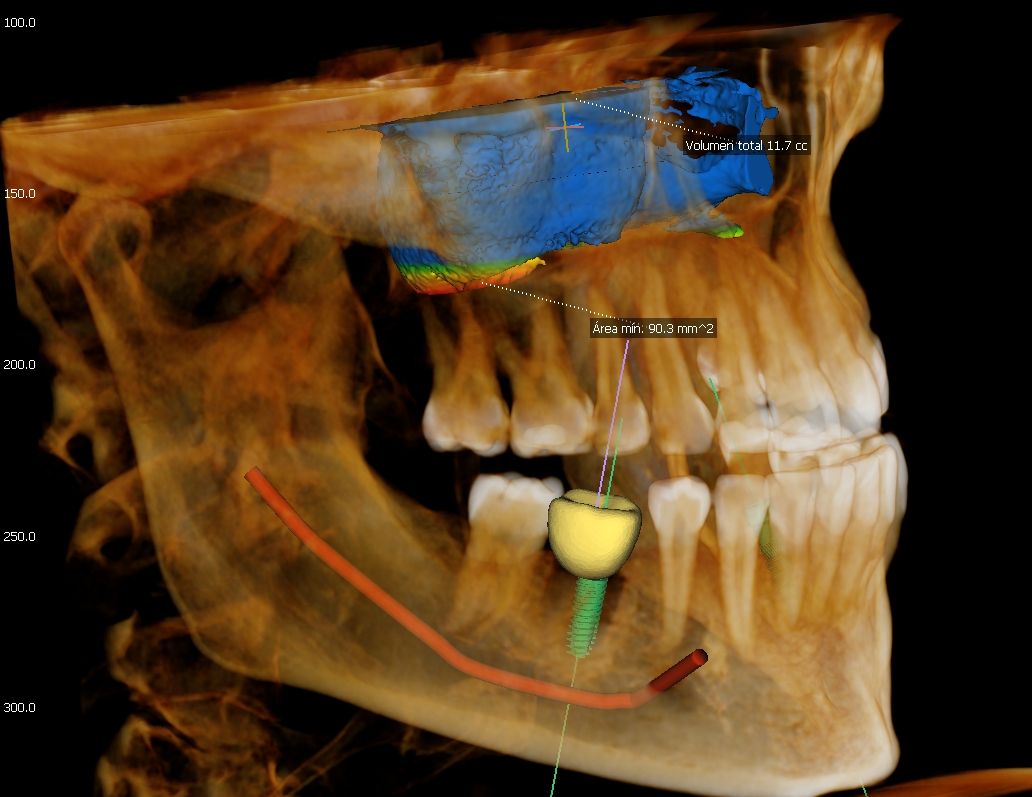

Green 16/18 ofrece una gama de campos de visión seleccionables. Multi FOV permite al usuario seleccionar el modo FOV óptimo y minimizar la exposición a áreas que no son la región de interés. Seleccione el tamaño adecuado de FOV entre 16×9/18×10, 12×9/13×10, 8×9 y 5×5 basado en una particular necesidad de diagnóstico. Cubre la región del arco completo, seno y la ATM izquierda / derecha y es adecuado para la mayoría de los casos de cirugía oral así como la cirugía de implantes múltiples. También puede medir el volumen de la vía aérea.